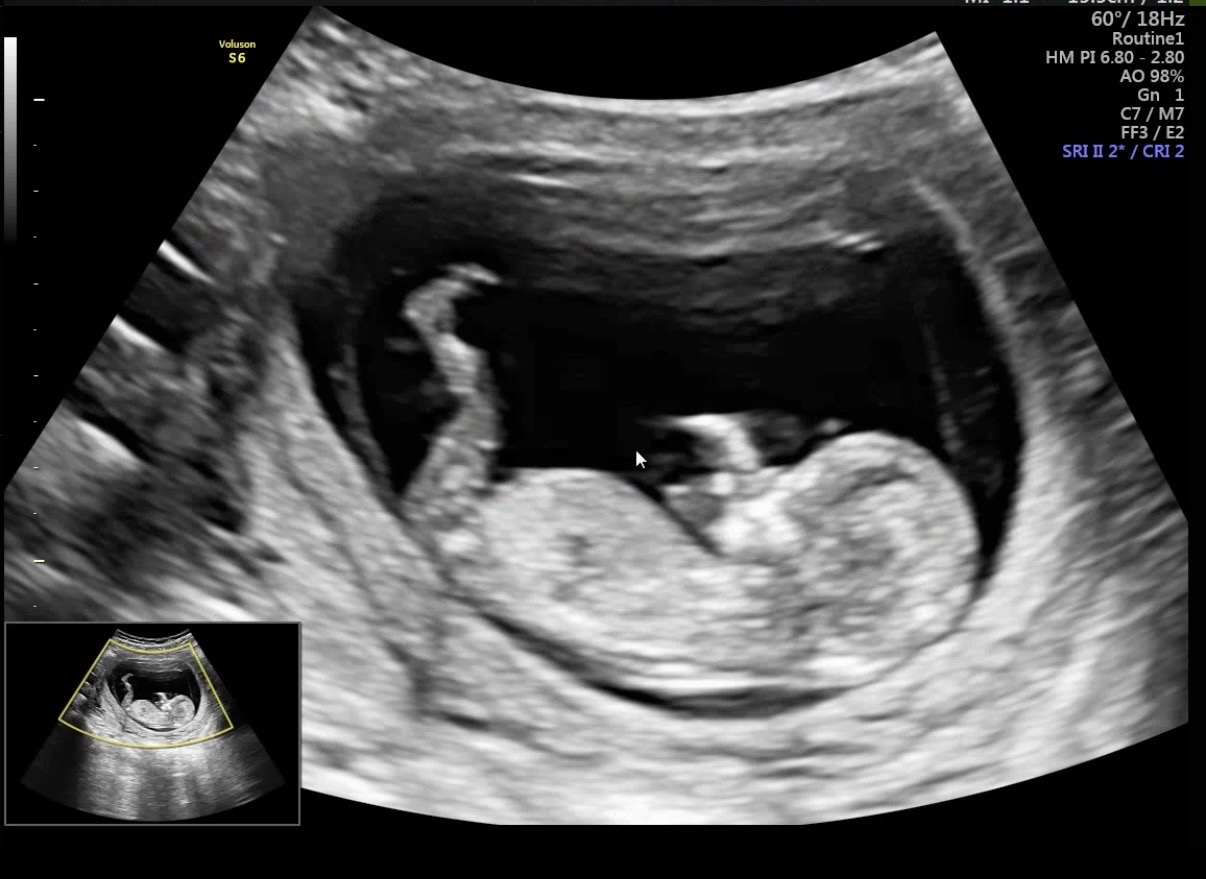

12주 성별,, 볼 수 있을까요?

이 사진으로 각도법,, 볼 수 있을까요?😂 많은 의견부탁드려요!